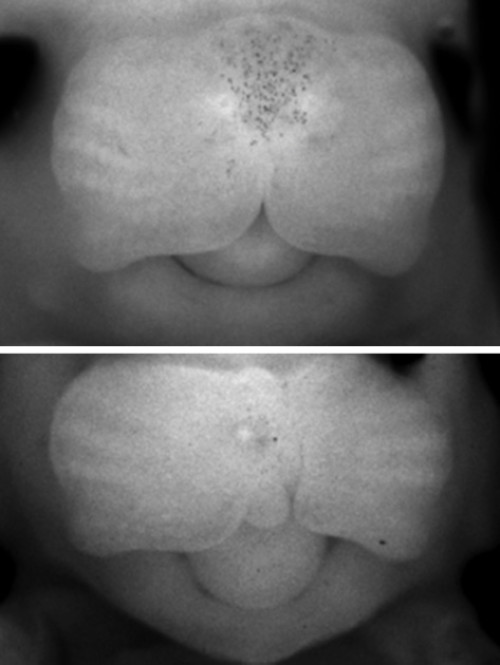

什么是唇裂?

唇腭裂是一个通俗的说法,它是指在人的是唇和颚部有裂口。其实这个名称并不能代表颅面部全部先天畸形。还包括牙槽突裂,另外还有完全性的唇裂还包括鼻底的裂开。再有由于牙槽突裂的存在,还会导致牙齿在发育当中的一个畸形。这种畸形它会影响到口腔和面部的很多的器官和功能。另外由于腭裂存在,还会影响到患者的听力。因此唇腭裂畸形是系统性、可能会影响多个方面的病变。这种病变一般来说是由于在发育过程中,由某种因素而导致形成口腔和面部发育的一些生发中心没有正常的连接和融合所导致的。唇腭裂是一种非常常见的先天的颌面部的发育畸形,一般来说在正常人群里面就达到1-2‰。亚州人群高于非洲人群。或者是600-700个人当中就会有一个唇腭裂小孩的发生。这种唇腭裂会在妊娠前的前三个月就出现,由于各种各样的因素,而影响胚胎的发育。这种畸形会影响到我们小朋友,除了形态和功能以外,它的影响还是非常深远。包括未来的发音,还有颌面部骨骼的发育,还有外形和功能的一些畸形和不正常。还有可能会影响到他参与社会行为,一些社会交往,反过来还会影响他的心理发育。因此这种唇腭裂的畸形是需要我们特别关注的。在胚胎发育的早期,唇、腭是由两侧组织往身体中线融合起来的,若不能正常融合,就会产生各种不同部位的裂缝,单纯嘴唇裂开,称为唇裂,既有唇部裂开又有腭部裂开称为唇腭裂,有时仅口腔内腭部裂开而外部正常,则称为腭裂。

什么是腭裂?

在胚胎发育的早期,唇、腭是由两侧组织往身体中线融合起来的,若不能正常融合,就会产生各种不同部位的裂缝,单纯嘴唇裂开,称为唇裂,既有唇部裂开又有腭部裂开称为唇腭裂,有时仅口腔内腭部裂开而外部正常,则称为腭裂。

什么是唇腭裂?